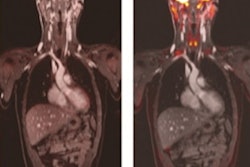

The researchers trained and validated the models using a dataset of 310 treatment plans from 53 abdominal cancer patients who had been treated with online adaptive, linac-based MRI-guided radiation therapy. Specifically, the ANN models were designed to predict 3D dose distributions based on the average of prior treatment plans.

"An estimated 3D dose prediction tailored to the specific anatomy of the day could provide a much-improved starting point for subsequent adapted plan development and optimization each fraction," the authors wrote. "The fact that our ANN models can provide a 3D dose prediction using contour information alone (a fully developed treatment plan is not needed) helps to bolster their potential use as novel inputs for alternative treatment planning strategies."